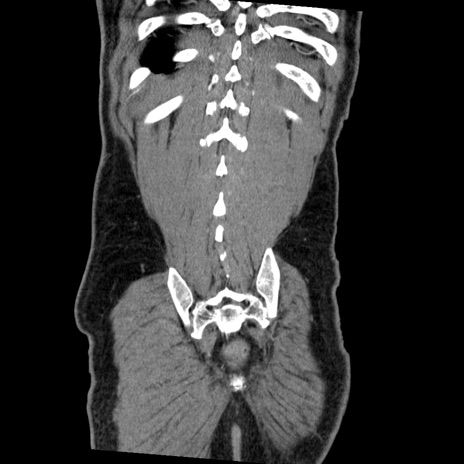

症例22(冠状断像)

【症例】50歳代男性

【主訴】腹痛

【現病歴】AVMからの被殻出血のため回復期リハ病棟入院中。 本日午後3時頃急に下腹部痛が出現した。

【既往歴】AVM、被殻出血、虫垂炎、高血圧

【身体所見】意識晴明、左半身不全麻痺、会話の理解は良好、36.5°C、腹部:膨隆、全体に板状硬、下腹部正中に圧痛点あり、反跳痛-、筋性防御不明、右下腹部にope scar

【データ】WBC 9400、CRP 0.06